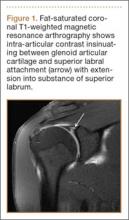

The MRA protocol differs from our routine noncontrast shoulder imaging. We perform a fat-saturated coronal oblique T1 sequence that maximizes the conspicuity of intra-articular contrast in the plane that optimally visualizes the superior labrum. Three planes of intermediate-weighted fast spin echo not only contrast the high-signal intra-articular fluid with the low-signal fibrocartilaginous labrum and the stratified intermediate signal of glenoid articular cartilage, but they also allow optimal assessment of the rotator cuff. In addition, we perform a fat-saturated coronal T2 sequence that highlights all fluid signal structures as well as edema.

SLAP tears appear on MRA as the insinuation of intra-articular contrast between the articular cartilage and the attachment of the superior labrum,3 within the substance of the labrum, or as detachment of the labrum from the glenoid rim4 (Figure 1). Findings can range from labral fraying to complete detachment with displacement. Tears can extend into other quadrants of the labrum, extend from a Bankart lesion, or involve the biceps tendon and/or the glenohumeral ligaments (Figures 2–4). Up to 10 types of SLAP tears have been described on arthroscopy. This classification scheme, however, is seldom helpful in the interpretation of SLAP tears on MRI. More important in guiding treatment is having a detailed description of the tear, including location, extent, and morphology, along with associated abnormalities.